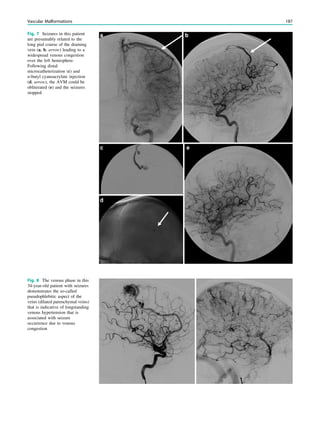

FLAIR sequences havea limited value in children up to 3 years due to their inherent T1 contrast and the lower signal to noise ratio of inversion recovery techniques (Fig. 2). In addition, the high heart rate of small children lead to more flow artifacts compared to adults. Magnetization transfer imaging is a helpful alternative imaging modality in children older than 3 years. Magneti- zation transfer is based on the interaction between mobile free water protons and macromolecular bound protons. An off-resonance radiofrequency pulse saturates protons bound to macromolecules, mainly in the myelin sheaths. Owing to spin–spin interactions, the saturation effect is transferred to surrounding mobile free protons. This results in a signal decrease from the mobile protons and an overall suppres- sion of signal from brain tissue. If a lesion has a low myelin fraction or contains abnormal myelin, signal suppression is lower than that in the healthy white matter. Thus, a lesion may appear as hyperintense on magnetization transfer images. Magnetization transfer images have been shown to be superior in the detection of white matter lesions in tuberous sclerosis complex (Pinto Gama et al. 2006; Woermann and Vollmar 2009), and similarly in some focal cortical dysplasias (Rugg-Gunn et al. 2003). During the first 3 years of life, high-resolution T2- weighed fast spin echo images have the highest diagnostic yield to detect and to delineate epileptogenic lesions (Fig. 1). Afterwards, FLAIR sequences are the most important ones. If a 3D FLAIR sequence cannot be acquired, we recommend acquiring FLAIR sequences in axial, coronal, and sagittal orientations. The first goal of MRI in epilepsy patients is the detection of an epileptogenic lesion. With careful MRI interpretation, lesions are visible without additional intravenous contrast medium injections. Contrast medium injections are usually needed to characterize a lesion but not to find it (Elster and Mirza 1991). Like in adults, we acquire contrast-enhanced T1-weighted spin echo sequences in epileptogenic lesions other than hippocampal sclerosis in order to characterize the lesion (Gaillard et al. 2009). References Barkovich AJ (2000) Concepts of myelin and myelination in neuroradiology. AJNR Am J Neuroradiol 21(6):1099–1109 Barkovich AJ, Kjos BO, Jackson DE Jr, Norman D (1988) Normal maturation of the neonatal and infant brain: MR imaging at 1.5 T. Radiology 166(1 Pt 1):173–180 Bernal B, Altman NR (2003) Evidence-based medicine: neuroimaging of seizures. Neuroimaging Clin N Am 13(2):211–224 Caraballo R, Cersosimo R, Galicchio S, Fejerman N (1997a) Benign infantile familial convulsions. Rev Neurol 25 (141):682–684 Caraballo RH, Cersosimo RO, Medina CS, Tenembaum S, Fejerman N (1997b) Idiopathic partial epilepsy with occipital paroxysms. Rev Neurol 25 (143):1052–1058 Cepeda C, Andre VM, Levine MS, Salamon N, Miyata H, Vinters HV, Mathern GW (2006) Epileptogenesis in pediatric cortical dysplasia: the dysmature cerebral developmental hypothesis. Epilepsy Behav 9(2):219–235. doi:10.1016/j.yebeh.2006.05.012 Cox RG, Levy R, Hamilton MG, Ewen A, Farran P, Neil SG (2011) Anesthesia can be safely provided for children in a high-field intraoperative magnetic resonance imaging environment. Paediatr Anaesth 21(4):454–458. doi:10.1111/j.1460-9592.2011.03528.x Elster AD, Mirza W (1991) Mr imaging in chronic partial epilepsy: role of contrast enhancement. AJNR Am J Neuroradiol 12(1):165–170 Eltze CM, Chong WK, Bhate S, Harding B, Neville BG, Cross JH (2005) Taylor-type focal cortical dysplasia in infants: some MRI lesions almost disappear with maturation of myelination. Epilepsia 46(12):1988–1992. doi:10.1111/j.1528-1167.2005.00339.x Falconer MA, Serafetinides EA, Corsellis JA (1964) Etiology and pathogenesis of temporal lobe epilepsy. Arch Neurol 10:233–248 Gaillard WD, Chiron C, Cross JH, Harvey AS, Kuzniecky R, Hertz- Pannier L, Vezina LG (2009) Guidelines for imaging infants and children with recent-onset epilepsy. Epilepsia 50(9):2147–2153. doi:10.1111/j.1528-1167.2009.02075.x King MA, Newton MR, Jackson GD, Fitt GJ, Mitchell LA, Silvapulle MJ, Berkovic SF (1998) Epileptology of the first-seizure presentation: a clinical, electroencephalographic, and magnetic resonance imaging study of 300 consecutive patients. Lancet 352(9133):1007–1011. doi:10.1016/S0140-6736(98)03543-0 OlafssonE,LudvigssonP,GudmundssonG,HesdorfferD,KjartanssonO, Hauser WA (2005) Incidence of unprovoked seizures and epilepsy in Iceland and assessment of the epilepsy syndrome classification: a prospective study. Lancet Neurol 4(10):627–634. doi:10.1016/ S1474-4422(05)70172-1 Osborne JP, Lux AL, Edwards SW, Hancock E, Johnson AL, Kennedy CR, Newton RW, Verity CM, O’Callaghan FJ (2010) The underlying etiology of infantile spasms (West syndrome): information from the United Kingdom Infantile Spasms Study (UKISS) on contemporary causes and their classification. Epilepsia 51(10):2168–2174. doi:10.1111/j.1528-1167.2010.02695.x Pinto Gama HP, da Rocha AJ, Braga FT, da Silva CJ, Maia AC Jr, de Campos Meirelles RG, Mendonca do RJI, Lederman HM (2006) Comparative analysis of MR sequences to detect structural brain lesions in tuberous sclerosis. Pediatr Radiol 36(2):119–125. doi: 10.1007/s00247-005-0033-x Rugg-Gunn FJ, Eriksson SH, Boulby PA, Symms MR, Barker GJ, Duncan JS (2003) Magnetization transfer imaging in focal epilepsy. Neurology 60(10):1638–1645 Schijns OE, Bien CG, Majores M, von Lehe M, Urbach H, Becker A, Schramm J, Elger CE, Clusmann H (2011) Presence of temporal gray-white matter abnormalities does not influence epilepsy surgery outcome in temporal lobe epilepsy with hippocampal sclerosis. Neurosurgery 68 (1):98–106; discussion 107. doi:10.1227/NEU. 0b013e3181fc60ff Schulte-Uentrop L, Goepfert MS (2010) Anaesthesia or sedation for MRI in children. Curr Opin Anaesthesiol 23(4):513–517. doi: 10.1097/ACO.0b013e32833bb524 van der Knaap M, Valk J (1990) MR imaging of the various stages of normal myelination during the first year of life. Neuroradiology 31(6):459–470 van der Knaap M, Valk J (2005) Magnetic resonance of myelination and myelin disorders. Springer Berlin Heidelberg, New York, pp 1–19 Vezina LG (2011) MRI-negative epilepsy: protocols to optimize lesion detection. Epilepsia 52(Suppl 4):25–27. doi:10.1111/j.1528-1167. 2011.03147.x Woermann FG, Vollmar C (2009) Clinical MRI in children and adults with focal epilepsy: a critical review. Epilepsy Behav 15(1):40–49. doi:10.1016/j.yebeh.2009.02.032 MRI of Children 41

• 48.

Functional MRI Jo¨rg Wellmer Contents 1Introduction.......................................................................... 43 1.1 Methodology of fMRI ........................................................... 44 1.2 Shortcomings of fMRI .......................................................... 44 1.3 Safe Clinical Application of fMRI for Different Indications.............................................................................. 46 References...................................................................................... 48 Abstract Functional magnetic resonance imaging (fMRI) is an abundantly applied tool for the preoperative localization and/orlateralizationofbrainfunctions.Itisnoninvasiveand therefore apparently without risk for patients. However, the particular risk of fMRI lies in several methodological limitations which can give rise to misinterpretations. These can result in fatal surgical decisions, for example, the resectionofundetectedfunctionalcortexorthe unnecessary sparing of tissue which has to be removed to achieve freedom from seizures. This chapter explains the method- ological aspects of fMRI with special focus on its limita- tions, but also gives recommendations for safe clinical application of fMRI. 1 Introduction Epilepsy surgery aims at achieving freedom from seizures by resecting the epileptogenic zone without causing unexpected neurological sequelae. A particular challenge is that in epi- lepsy patients the functional anatomy of sensorimotor, lan- guage, and memory systems shows interindividual variability (Helmstaedter et al. 1997; Staudt 2010). The reasons for in- trahemispheric or interhemispheric shift of functions can be interictal or ictal epileptic discharges or morphological lesions (Staudt 2010; Janszky et al. 2003; Weber et al. 2006). Traditionally, inactivating methods such as the Wada test (Baxendale 2009) or electrical stimulation mapping (ESM) (Berger et al. 1989; Hamberger 2007) are applied to identify the individual functional anatomy. These methods produce a transient functional lesion and indicate whether surgery in the inactivated area would cause a persisting functional deficit. Both methods carry some risk of morbidity although for the Wada test large studies have shown a risk of permanent morbidity of only around 0.5% (Loddenkemper et al. 2008; Haag et al. 2008). Also, extraoperative electrical stimulation has an acceptable risk–benefit ratio (Wellmer et al. 2012). J. Wellmer (&) Ruhr-Epileptology, Department of Neurology, University Hospital Knappschaftskrankenhaus Bochum, Germany e-mail: joerg.wellmer@kk-bochum.de H. Urbach (ed.), MRI in Epilepsy, Medical Radiology. Diagnostic Imaging, DOI: 10.1007/174_2012_563, Ó Springer-Verlag Berlin Heidelberg 2013 43

• 49.

However, several alternativemethods have been devel- oped which allow noninvasive lateralization and localiza- tion of cerebral functions. The most abundantly distributed is functional MRI (fMRI). As most noninvasive methods, fMRI is an activation method (Desmond and Annabel Chen 2002). Patients are instructed to perform specific tasks fol- lowing a strict protocol, and via a surrogate parameter (spatial distribution of activation-related cerebral perfusion changes) the intracerebral localization of the tested function is determined (Fig. 1). In fact, many studies have described congruence between fMRI and the Wada test (Binder et al. 1996) or ESM (FitzGerald et al. 1997; Yetkin et al. 1997), in particular for language lateralization and localization. Yet, fMRI has several methodological limitations which can affect its validity. These limitations have to be known to physicians who apply or request fMRI in a presurgical setting. Therefore, this chapter addresses the methodologi- cal aspects and shortcomings of fMRI before finally giving recommendations regarding its safe clinical application. For reasons of clarity, this chapter concentrates on fMRI for sensorimotor, language, and memory functions. 1.1 Methodology of fMRI For fMRI the patient is positioned in a standard MRI scanner. Following a predefined time schedule, the patient has to perform simple motor to complex cognitive tasks alternating with control conditions. Instructions are given to the patient either auditorily (through headphones) or visually (via a mirror or goggles). For fMRI of the sensory system, tactile stimuli are applied to the patient. In response to the execution of the task, neuronal activity and oxygen consumption are elevated in areas associated with this task (e.g., finger-tapping results in increased neuronal activity in the hand motor cortex). The oxygen consumption results in a transient increase in deoxyhemoglobin (desoxy- Hb), but neurovascular coupling leads to an immediate regional surplus of oxyhemoglobin (oxy-Hb). The relative oxy-Hb surplus persists until shortly after termination of the task, then the oxy-Hb/desoxy-Hb ratio drops back to the baseline. Since oxy-Hb is more diamagnetic than desoxy-Hb, regional oxy-Hb hyperperfusion leads to subtle magnetic changes which can be identified in serial T2*-weighted images (for review, see Logothetis 2002). By statistical parametric mapping (http://www.fil.ion.ucl.ac.uk/spm/) or other techniques, one can statistically evaluate subsequent series of images acquired during the active condition and the control condition. Areas that show changes in magnetic signal temporally associated with the protocol-defined course of the active and the control condition are identified and visualized. 1.2 Shortcomings of fMRI Although the principle of fMRI is simple and logical, there are a number of limitations to this technique which call for care when interpreting activation patterns. Six exemplary limitations are as follows. Fig. 1 Principle of fMRI, blocked design. Panel A: blood oxygena- tion level dependent (BOLD) effect: following a defined stimulus the oxygen-need is increased in areas associated with stimulus processing. This causes a regional transient decrease of oxy-Hb (1), but due to the neurovascular response the regional supply with oxy-Hb increases, exceeding the oxygen-consumption (2). After the stimulus processing ends (3) excess perfusion stops and the oxy-Hb level returns to baseline. Panel B: Oxy-Hb is more diamagnetic than desoxy-Hb. The regional oxy-Hb hyperperfusion leads to subtle magnetic changes which can be identified in serial T2* weighted images. By statistical comparison of MRI-scans acquired during the active and the control condition, stimulus-associated T2*-changes can be identified and visualized, for example overlaid to a morphological MRI scan of the patient. Alternative to the blocked design shown here event-related protocols can be applied. However, they are statistically less robust in clinical routine 44 J. Wellmer

• 50.